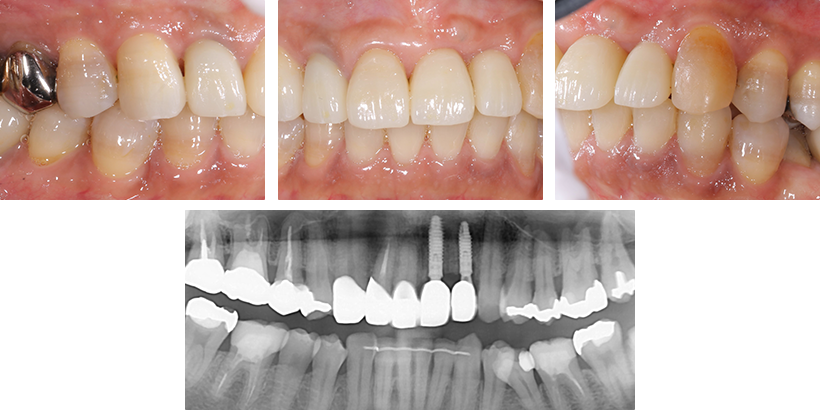

こちらではインプラントと歯周病治療の症例をご紹介いたします。治療のご参考にご覧下さい。

インプラント症例